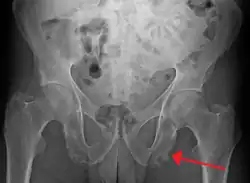

| Enthesopathy of the pelvis likely due to ankylosing spondylitis | |

An enthesopathy refers to a disorder involving the attachment of a tendon or ligament to a bone.[1] This site of attachment is known as the enthesis (pl. entheses). If the condition is known to be inflammatory, it can more precisely be called an enthesitis.